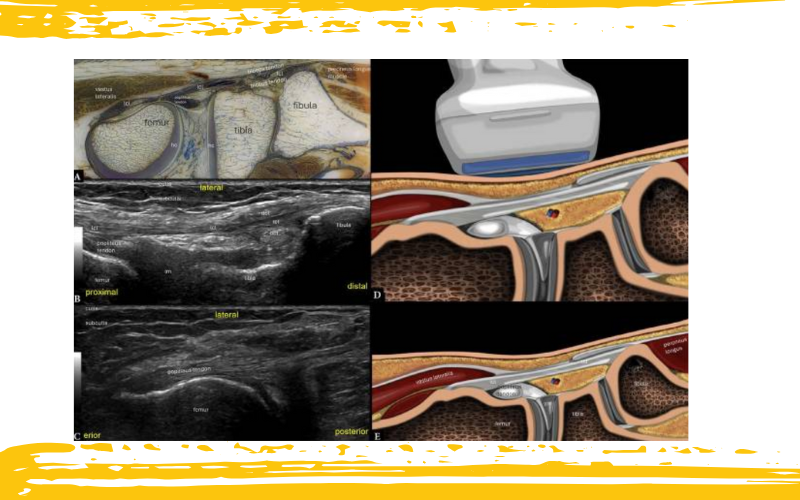

Rodilla lateral. Corte histológico (A) y ecografías (B, C). Ilustraciones con la posición de la sonda en plano longitudinal suprarrotuliano (D–E).

En B, el transductor se coloca sobre el eje largo del ligamento colateral lateral (LCL). Se observa que el tendón distal del bíceps (DBT) se bifurca justo proximal a su inserción, de modo que una porción queda superficial y la otra profunda con respecto al ligamento. Esta es una apariencia normal.

En C, al rotar el transductor 90° desde la posición de la imagen B, se visualiza el eje largo proximal del tendón del poplíteo.

lm – menisco lateral; hc – cartílago hialino.